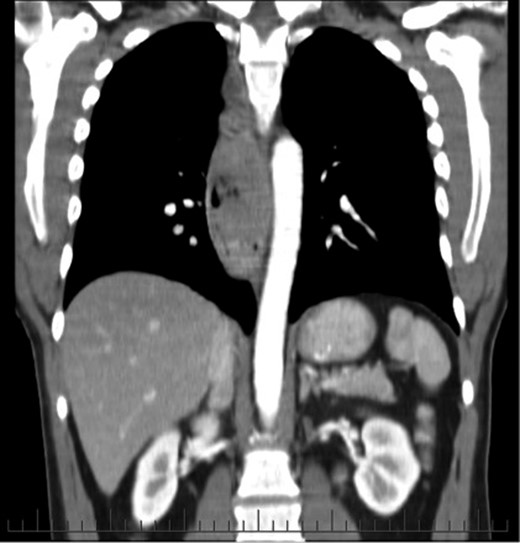

A 75-year-old male presented with a 2-month history of dysphagia, odynophagia and retrosternal post-prandial pain. He had no relevant medical history, and physical, dermatological and ophthalmological examinations proved unremarkable. Barium swallow showed filling defects in the distal oesophagus and subsequent endoscopy found an 8-cm bluish exophytic oesophageal lesion with numerous adjacent satellite lesions and moderate luminal stricturing (Fig. 3). A biopsy result indicated a poorly differentiated malignant melanoma. CT and PET showed an enlarged mediastinal node (not FDG avid) with no evidence of metastases.

An endoscopic view of the oesophageal melanoma with numerous adjacent satellite lesions.